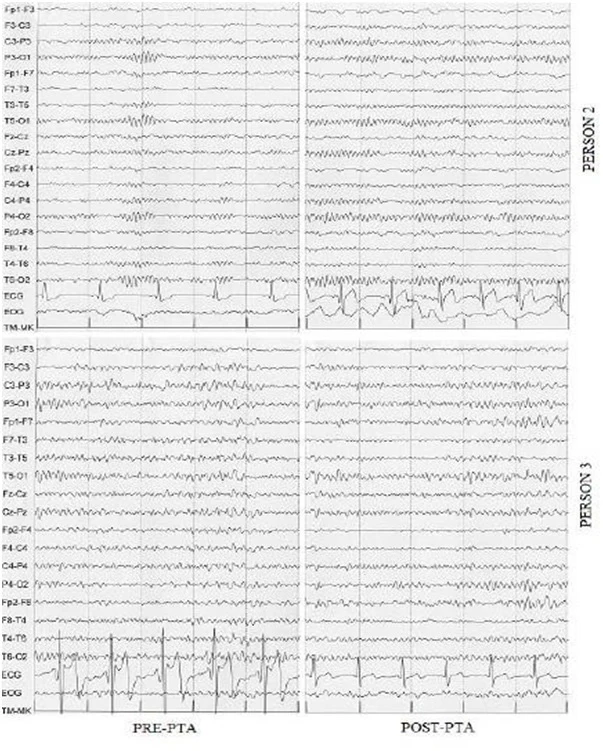

Metodi: Sette pazienti con diagnosi di CCSVI ed emicrania cronica, con o senza altri sintomi, sono stati sottoposti a angioplastica transluminale percutanea (PTA) delle vene giugulari interne. Tutti hanno eseguito risonanza magnetica venografica e/o ecocolordoppler prima della PTA, sette EEG preoperatori e cinque EEG di controllo post-PTA. L’intensità del dolore è stata valutata con una scala numerica prima e dopo l’intervento.

Risultati: Tutti i pazienti hanno mostrato un miglioramento del flusso ematico giugulare dopo PTA. In cinque pazienti su sette è stato osservato un miglioramento del ritmo alfa cerebrale all’EEG post-operatorio e tutti hanno riportato una significativa riduzione del dolore.

Conclusioni: Queste osservazioni preliminari suggeriscono una stretta associazione tra emicrania cronica, anomalie venose intra- ed extracraniche e alterazioni EEG, e indicano la venoplastica come possibile approccio terapeutico da approfondire.